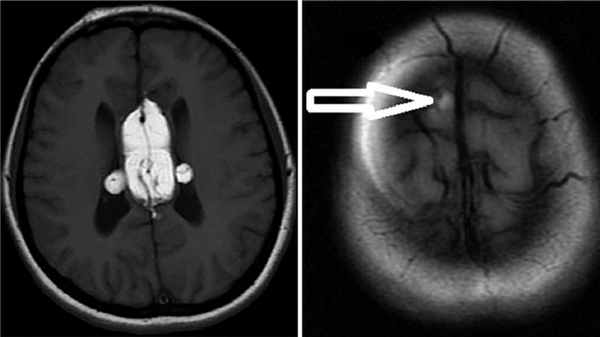

(Слева) На рисунке показано сосудистое образование почки с видимыми жировым и мягкотканным компонентами. Обратите внимание на крупные «питающие» артерии. Такая гиперваскуляризация предрасполагает эти опухоли к спонтанным кровотечениям.

(Справа) УЗИ в сагиттальной плоскости: эхогенное образование в коре верхнего полюса левой почки вследствие случайно обнаруженной ангиомиолипоме (АМЛ). Цветовой поток в данном образовании отсутствует. (Слева) КТ без контрастирования, аксиальная проекция: у этого же пациента выявлено образование жировой плотности В в коре верхнего полюса левой почки. Данные признаки характерны для ангиомиолипомы (АМЛ).

(Справа) МРТ, постконтрастное Т1, режим подавления сигнала от жировой ткани, аксиальная проекция: обнаружена ангиомиолипома (АМЛ), которая распространяется в околопочечное пространство. Дефект коры (признак «желобка»), указывающий на происхождение ангиомиолипомы (АМЛ) из ткани почки. Крупный сосуд продолжается в новообразование из почки.